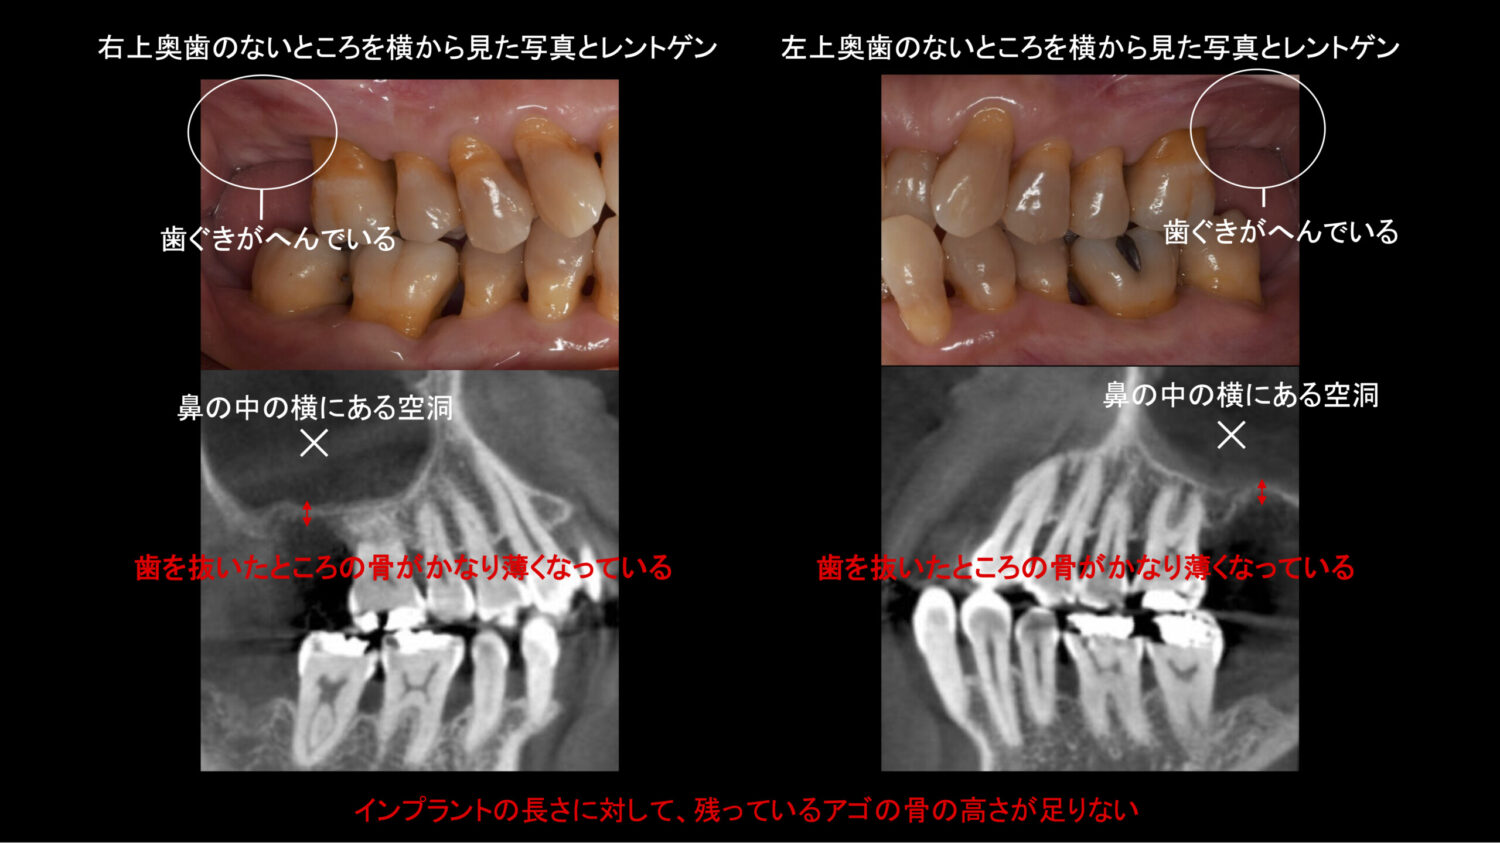

初診時のお口の中の写真とレントゲン写真

左右上の奥歯の欠損部は、歯ぐきが凹んでおり、やや硬い歯ぐきも少ない状態でした。レントゲンを撮ると、鼻の骨の横にある空洞と歯を抜いた部分のアゴの骨のフチが非常に近く、入れたいインプラントの長さよりもアゴの骨の高さが明らかに不足し、歯を抜いた部分の骨が非常に薄い状態でした。